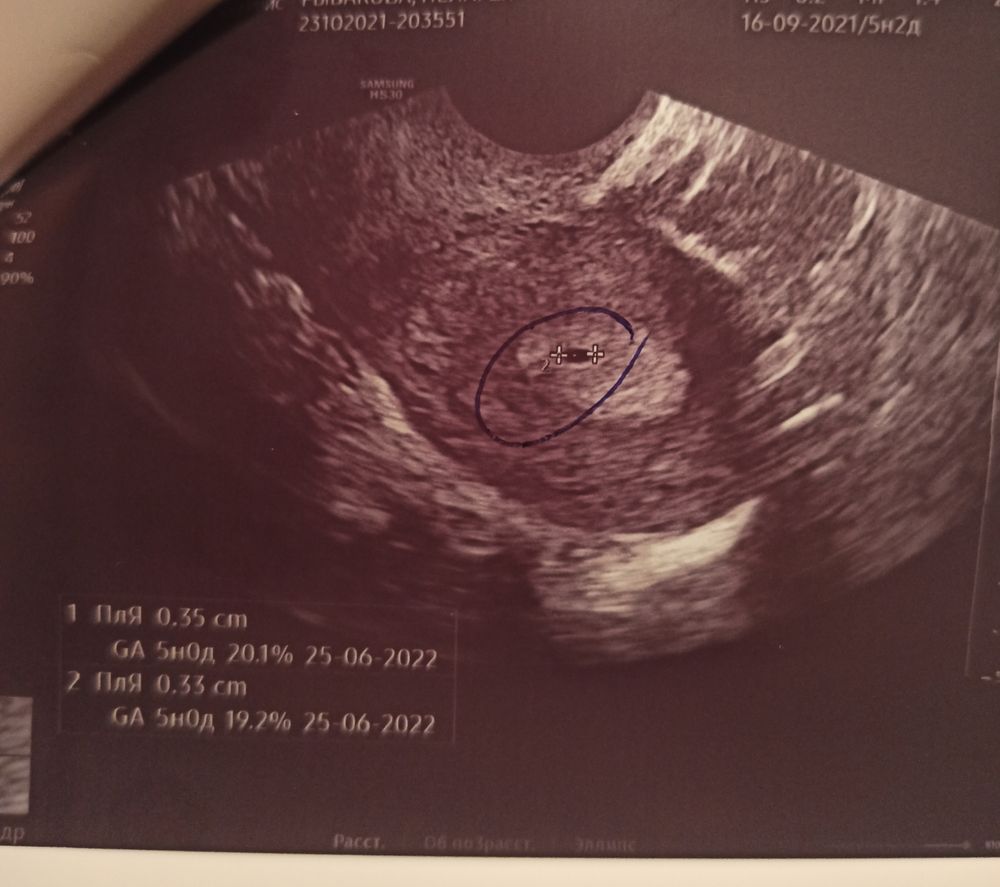

На УЗИ плодное яйцо в матке. ХГЧ отрицательный.

Девочки, может ли быть это киста или беременность? Я вообще не знаю что думать. УЗИ показывает одно, а тесты и ХГЧ отрицает. В платной клинике делала УЗИ, беременность поставили под вопросом. Сегодня пойду в гинекологию на полноценный осмотр. Очень волнуюсь.